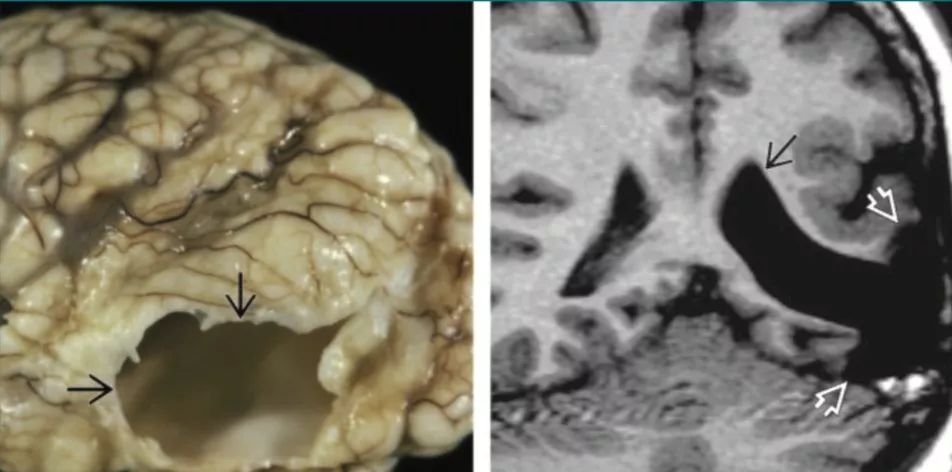

图7 脑穿通畸形

左图中尸检可见颞叶获得性大孔囊肿,与侧脑室颞角相通(箭头)。右图冠状位T1WI像显示左侧颞角扩大(黑色箭头),与周围的空洞性囊肿(白色箭头)相通,囊肿延伸到大脑表面。